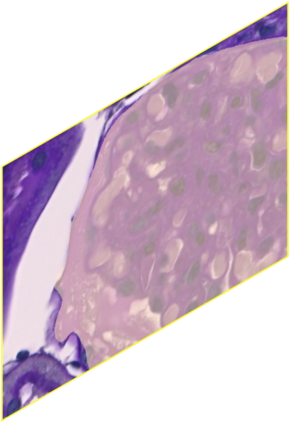

In digital pathology, the traditional method for deep learning-based image segmentation typically involves a two-stage process: initially segmenting high-resolution whole slide images (WSI) into smaller patches (e.g., 256x256, 512x512, 1024x1024) and subsequently reconstructing them to their original scale. This method often struggles to capture the complex details and vast scope of WSIs. In this paper, we propose the holistic histopathology (HoloHisto) segmentation method to achieve end-to-end segmentation on gigapixel WSIs, whose maximum resolution is above 80,000$\times$70,000 pixels. HoloHisto fundamentally shifts the paradigm of WSI segmentation to an end-to-end learning fashion with 1) a large (4K) resolution base patch for elevated visual information inclusion and efficient processing, and 2) a novel sequential tokenization mechanism to properly model the contextual relationships and efficiently model the rich information from the 4K input. To our best knowledge, HoloHisto presents the first holistic approach for gigapixel resolution WSI segmentation, supporting direct I/O of complete WSI and their corresponding gigapixel masks. Under the HoloHisto platform, we unveil a random 4K sampler that transcends ultra-high resolution, delivering 31 and 10 times more pixels than standard 2D and 3D patches, respectively, for advancing computational capabilities. To facilitate efficient 4K resolution dense prediction, we leverage sequential tokenization, utilizing a pre-trained image tokenizer to group image features into a discrete token grid. To assess the performance, our team curated a new kidney pathology image segmentation (KPIs) dataset with WSI-level glomeruli segmentation from whole mouse kidneys. From the results, HoloHisto-4K delivers remarkable performance gains over previous state-of-the-art models.